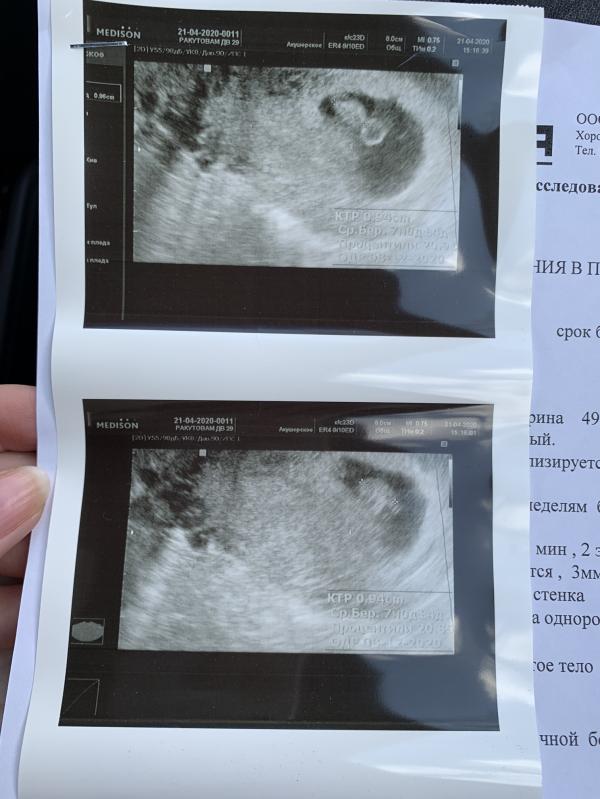

Захожу в кабинет узи сегодня, ложусь, меня трясет от страха. Только бы бусина была живой и сердечко билось!

Доктор водит датчиком две минутки и спрашивает:

-вы на узи были?

-да, в 4 недели. Плодное яйцо увидели и все.

-одно?

-😳 ... да, одно.. ????

- а эмбриона два..

- чтооо???? Чтооо???

-да! Я еще подумала, почему два желточных мешочка, а потом увидела два сердечка!! Вот смотри!

Я в шоке... я лежу и плачу... ...